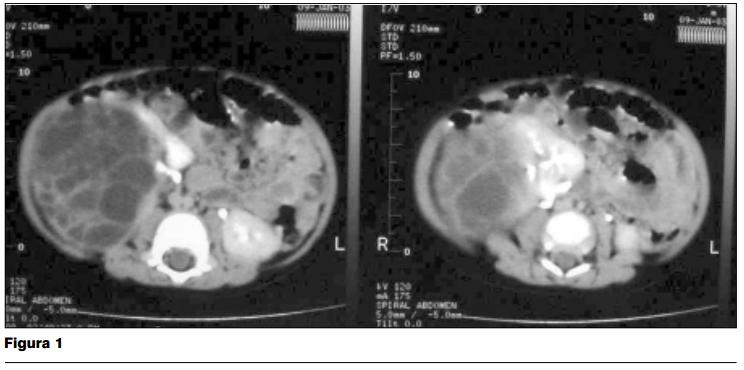

Tomografía abdominal evidencia imágenes compatibles con nefroma quístico multilocular (figura 1).

Centellograma con DMSA: riñón derecho con evidencia centellográfica de un extenso proceso sustitutivo que involucra los dos tercios superiores del parénquima renal, con una función renal diferencial de 68% para el riñón izquierdo y 32% para el riñón derecho. Hemograma: glóbulos blancos 14 300, linfocitos 53%, glóbulos rojos 4.820.000, hemoglobina 9,5 g/dl, hematocrito 30,4%, volumen corpuscular medio 63 fl, plaquetas 587.000 elementos/mm3. Lámina: anisocitosis, microcitosis, hipocromía.